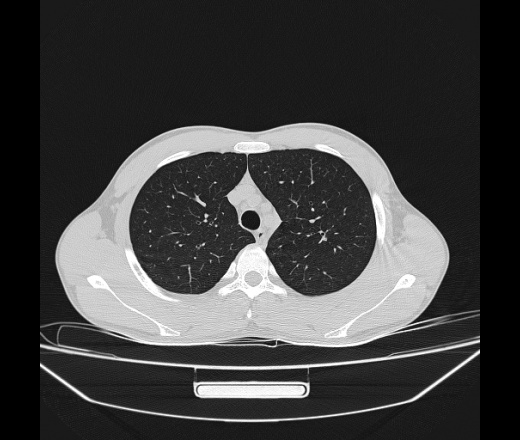

Молодой парень 18 лет, призывник, при прохождении ФЛС на верхушек левого легкого выявили очаги средней интснисвности с нечеткими контурами, тяжи. Сделали бок и томограммы 6-7-8. Везде описывают как очаговый твс. Вижу только перибронхиальный фиброз. Что за изменения в бронхах, указано нижи стрелками, тоже перибронхиальный?